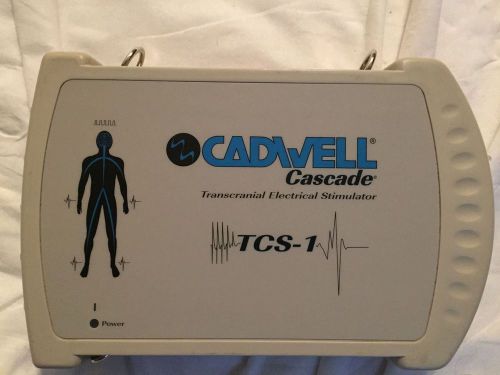

Cadwell Cascade Transcranial Electrical Stimulator